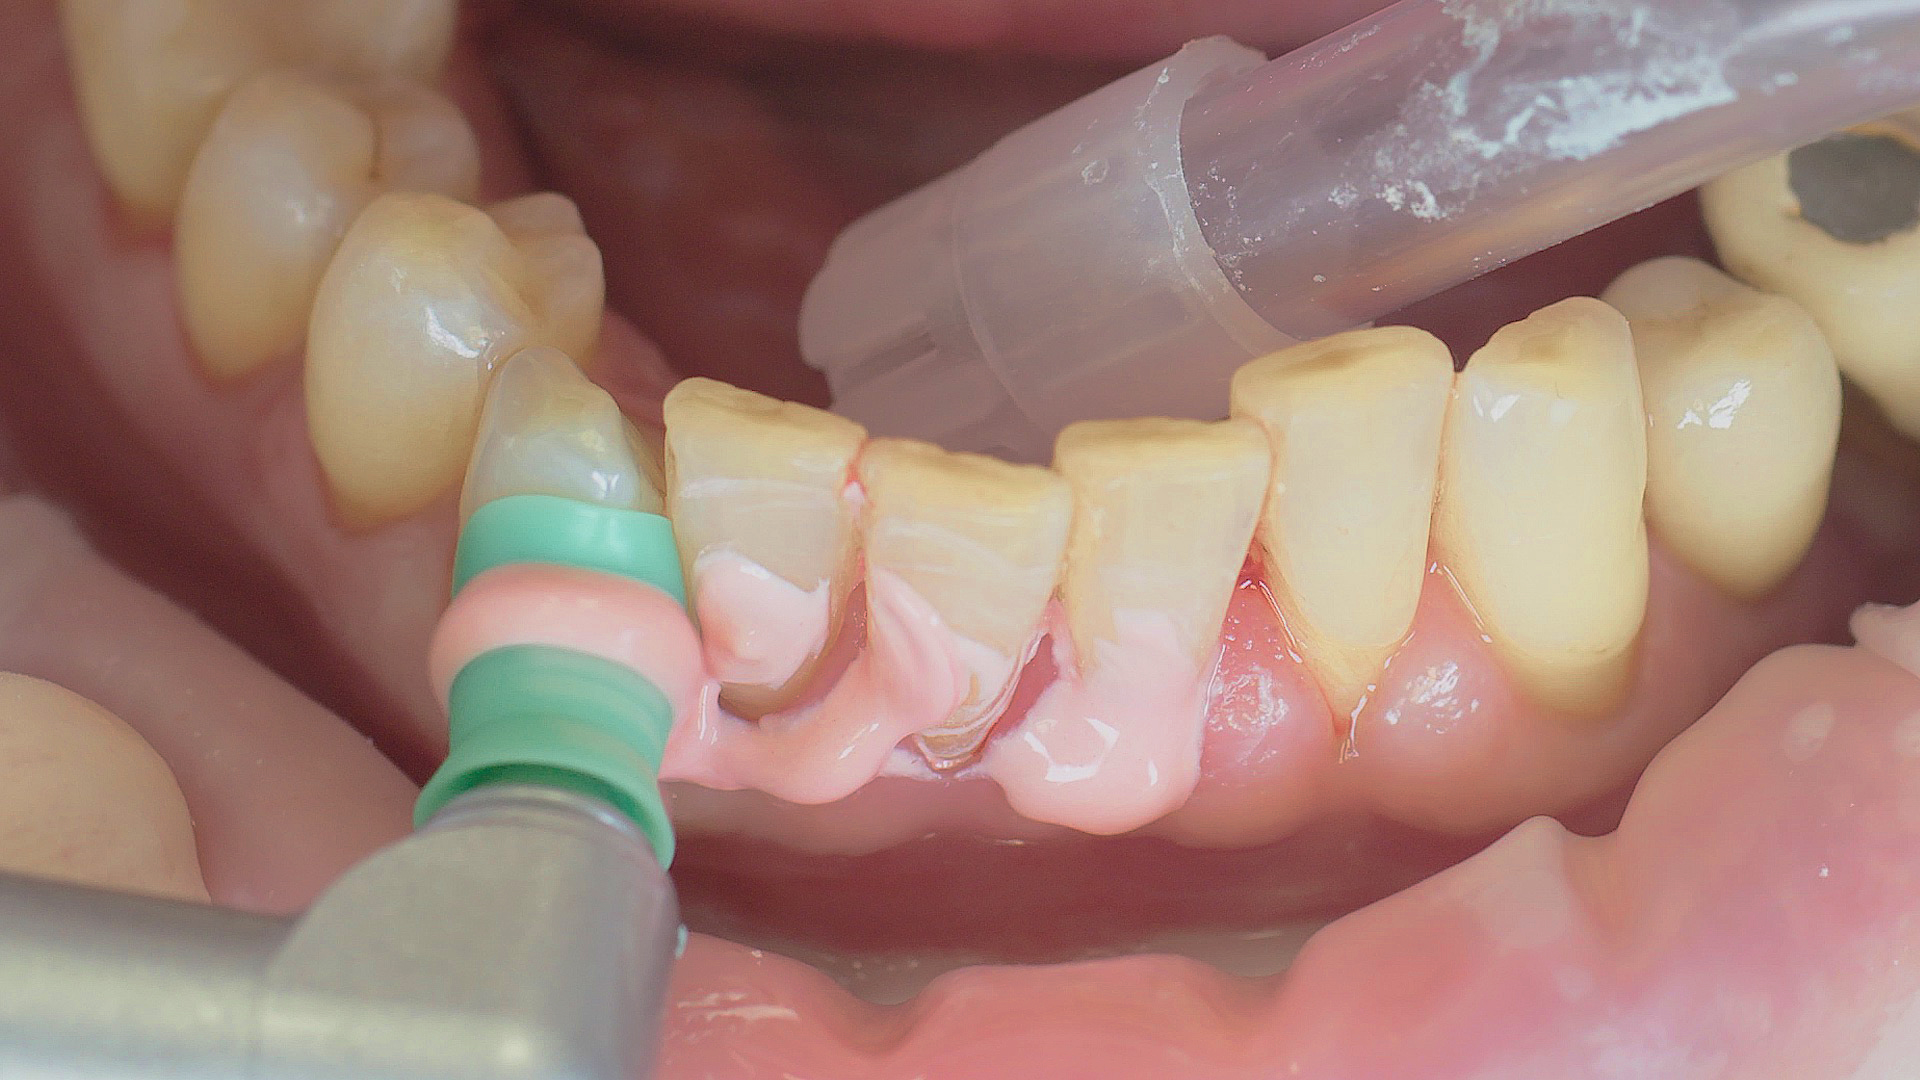

Tous les examens dentaires reposent sur l’étude des antécédents médicaux détaillés, associée à un diagnostic ciblé contenant le plus de détails possible. Le chirurgien-dentiste enregistre les facteurs de risque systémiques tels que le diabète ou le tabagisme et identifie toute augmentation de la tendance potentielle à l'inflammation.[3] Les tissus durs et mous sont examinés et les poches parodontales sont sondées dans le cadre d’un test de dépistage selon le PSR (Periodontal Screening and Recording). En cas de résultats anormaux, l’état du parodonte est ensuite enregistré et un traitement est démarré si nécessaire. Ce traitement débute par la gestion professionnelle du biofilm à l'aide par exemple de cupules rotatives et de composés de polissage (Fig. 1) et comporte des instructions complètes sur l’hygiène buccodentaire. Les systèmes à ultrasons restent une alternative ou un complément efficace aux instruments manuels pour le détartrage subgingival et la gestion du biofilm (présentation du Pr Dr Ulrich Schlagenhauf ;

Une bonne hygiène buccodentaire personnelle et une gestion professionnelle du biofilm, par exemple à l'aide de cupules et de brossettes, sont favorables à la santé parodontale et péri-implantaire.

Fig. 1 : Une bonne hygiène buccodentaire personnelle et une gestion professionnelle du biofilm, par exemple à l'aide de cupules et de brossettes, sont favorables à la santé parodontale et péri-implantaire.